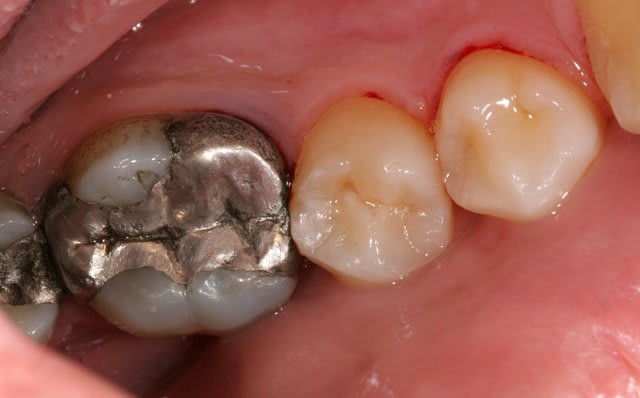

Plus sérieusement, je vous trouve assez sévère avec l'étanchéité des couronnes. Certes, elles ne sont pas parfaites. Il y a des encoches en mésiale de 22 et distal de 21...due au passage de brossette. Il n'y a absolument pas de reprise carieuse. Ce qui, je suis d'accord aurait contre-indiqué la chirurgie en première intention.

> 2)ton rapport couronne racine est totalement défavorable heureusement que les

> ccm sont solidarisées

Je pense que c'est la raison de ne pas déposer : éviter qu'elle se retrouve tout seule. Et puis la patiente ne voulait pas tout casser.

> 3)ton atteinte en mésiale remonte plus haut que ta résection.

C'est vrai. J'ai passé du temps avec mon insert à nettoyer cette zone (et tout autour d'aileurs, notamment en palatin).